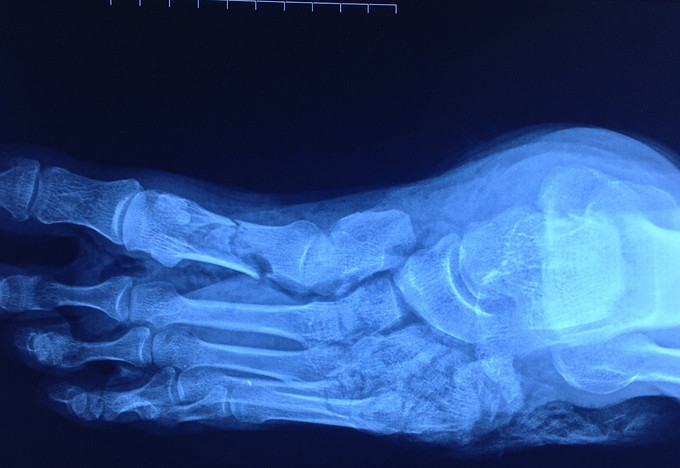

查体 辅查

神清,贫血貌,足畸形、毁损。

诊断:足挤压伤、毁损伤。多发骨折,血管神经肌腱损伤。 急诊行再植术。术中吻合足背动脉、大隐静脉。术后前足血运较好,第1趾皮温低,余四趾皮温尚可。足背皮肤血运不良。

术后11天,足发生坏死,血运无,皮肤色灰暗。足背皮肤已经完全坏死,变黑干瘪。吻合血管部位皮肤软组织条件制约再植的成功率。